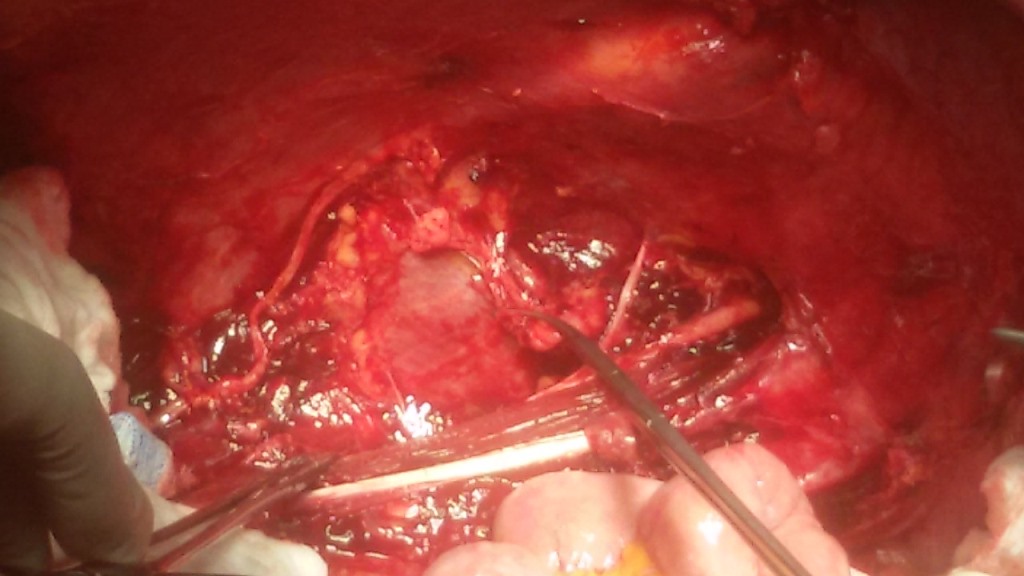

Першочерговою моєю ціллю була операційна, де інтенсивну програму забезпечував молодий та надзвичайно талановитий завідувач відділення Даніель Піндяк, за спиною якого багато закордонних стажувань та визнання як одного з кращих онкохірургів цієї країни. Власне завдяки йому в мене була можливість розширити свої знання в галузі сучасних стандартів онкологічних розширених лімфодисекцій при раку шлунка та підшлункової залози. Складність оперативних втручань, які він виконує, говорить сама за себе: панкреатодуоденальні резекції, RAMS, гастректомії з D2 лімфодисекцією та розширеною лімфодисекцією, дистальні та тотальні резекції стравоходу, судинні реконструкції при місцево-розповсюджених процесах, резекції печінки, широкі заочеревинні лімфаденектомії та багато інших.

Деякі з таких оперативних втручань виконуються і в нашому хірургічному відділенні Тернопільської університетської лікарні. Проте кожне нове стажування і асистування під час подібних операцій за кордоном додають нового досвіду і суттєво покращують навички.